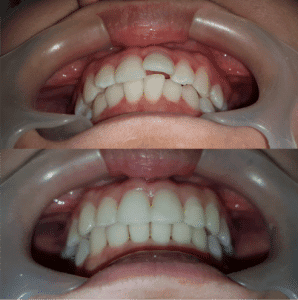

ด้วยประสบการณ์จัดฟันมานาน และความใจดีของคุณหมอ เราจึงมีเคสตัวอย่างมากมาย แม้แต่เคสฟันเกมากๆ ฟันห่างเยอะ เคสถอนฟัน คุณหมอยินดีให้คุณได้ดูเทียบเคียงผลการรักษาก่อนตัดสินใจ

เราจะใช้เครื่องสแกนฟัน ชื่อ Itero ชนิดพิเศษของ Invisalign สามารถบันทึกลักษณะฟันได้ทั้งปาก แล้วยังออกแบบและประมวลผลการจัดฟันเบื้องต้นได้ในเวลาอันรวดเร็ว คุณสามารถดูและเปรียบเทียบ Before และ After ของการจัดฟัน ได้ในทันทีที่สแกนเสร็จ